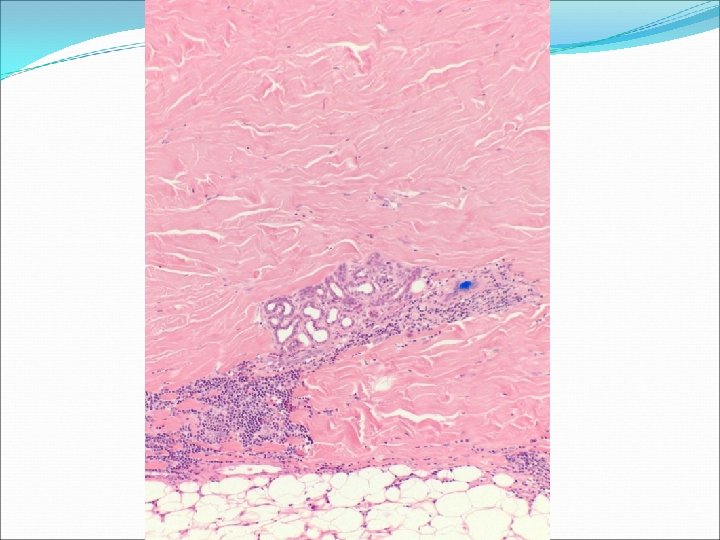

�Case number: 187 �Female 65 yrs. �Extending atrophic white plaque left anterior iliac region.

�Case number: 187 �Female 65 yrs. �Extending atrophic white plaque left anterior iliac region. �Macro: Elliptical piece of skin 20 x 6 x 6 mm.

Most popular diagnosis Morphoea